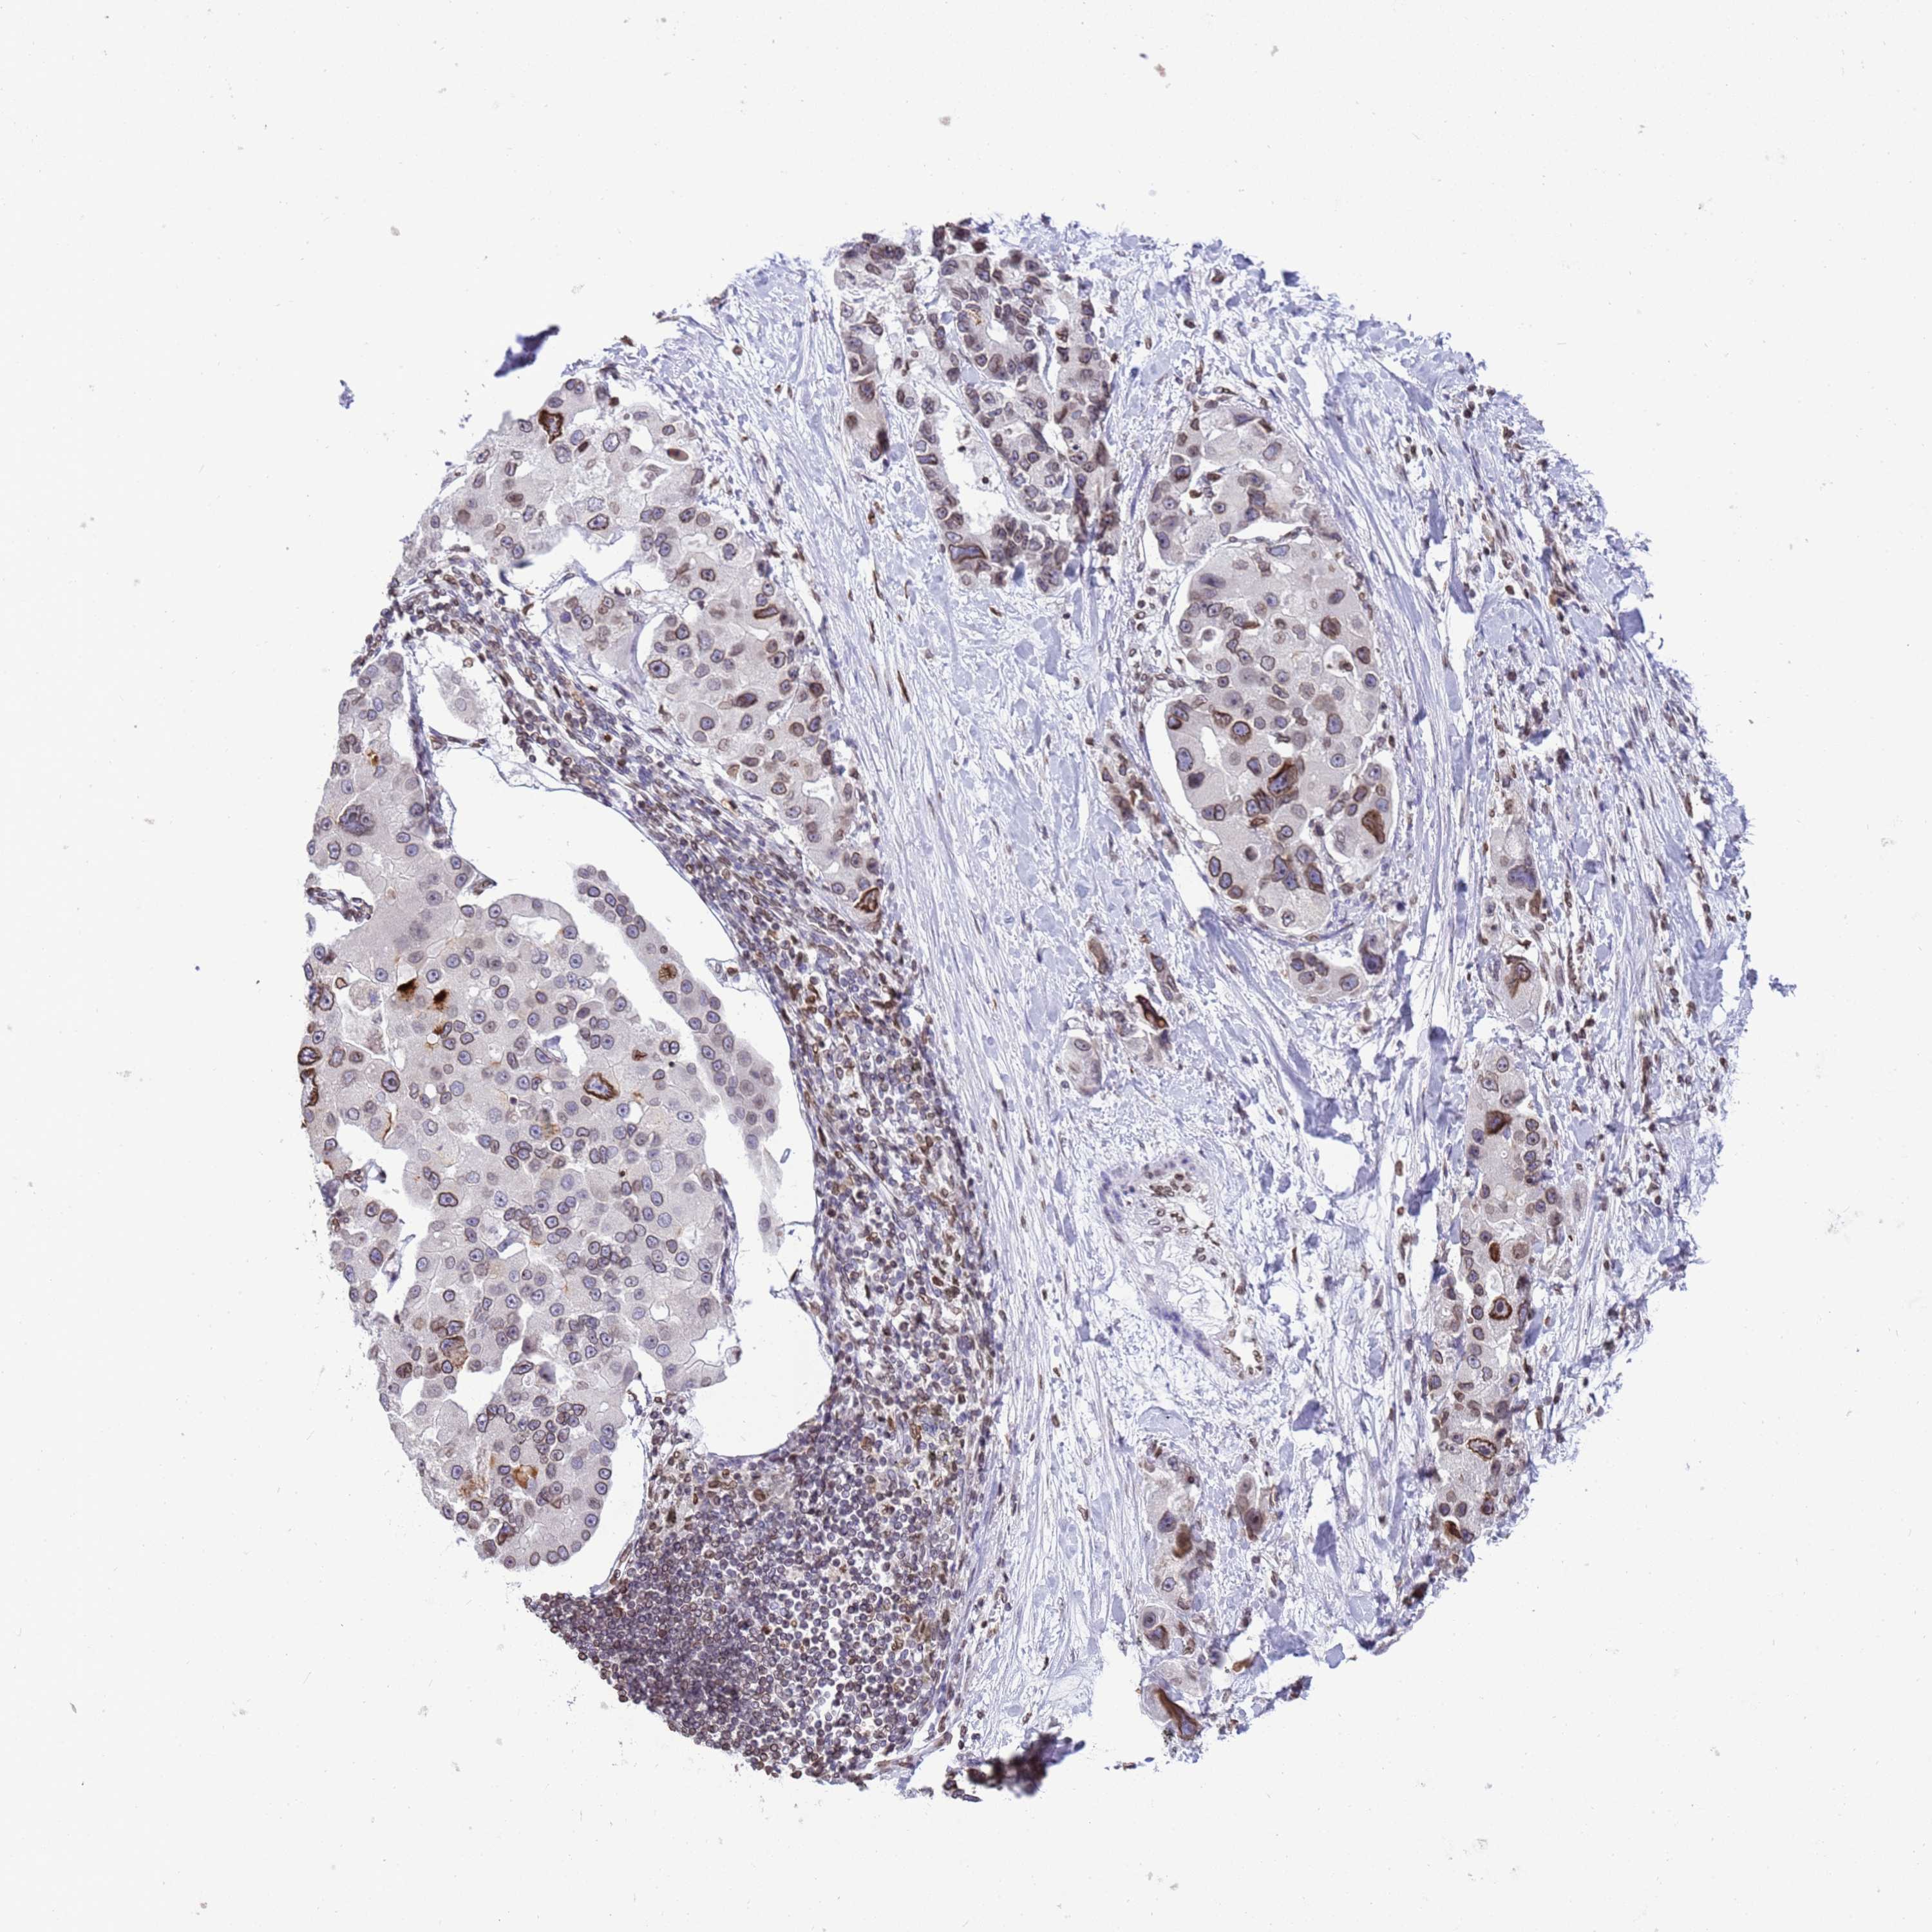

LUNG ADENOCARCINOMA (TCGA) - Interactive survival scatter ploti

The Survival Scatter plot shows the clinical status (i.e. dead or alive) for all individuals in the patient cohort, based on the same data that underlies the corresponding Kaplan-Meier plots. Patients that are alive at last time for follow-up are shown in blue and patients who have died during the study are shown in red.

The x-axis shows the expression levels (FPKM) of the investigated gene in the tumor tissue at the time of diagnosis. The y-axis shows the follow-up time after diagnosis (years). Both axes are complimented with kernel density curves demonstrating the data density over the axes. The top density plot shows the expression levels (FPKM) distribution among dead (red) and alive patients (blue). The right density plot shows the data density of the survived years of dead patients with high and low expression levels respectively, stratified using the cutoff indicated by the vertical dashed line through the Survival Scatter plot. This cutoff is automatically defined based on the FPKM cutoff that minimizes the p-score. The cutoff can be changed by dragging the vertical line or by entering a cutoff value in the square labeled "Current cut-off".

Under the Survival Scatter plot the p-score landscape (black curve; left axis) is shown together with dead median separation (red curve; right axis). Dead median separation is the difference in median mRNA expression between patients who have died with high and low expression, respectively. It is calculated as follows: median FPKM expression of dead patients with high expression - median FPKM expression of dead patients with low expression. This is intended to aid the user in visually exploring custom cutoffs and the associated p-scores and dead median separation.

Individual patient data is displayed and can be filtered by clicking on one or more of the category buttons on the top of the page. Categories describing expression level and patient information include: high, low, alive, dead, female, male and tumor stages. The scale of the x-axis can be toggled between linear and log-scale by clicking on the "x log" button. Mouse-over function shows TCGA ID, patient information and mRNA expression (FPKM) for each patient.

& Survival analysisi

Kaplan-Meier plots summarize results from analysis of correlation between mRNA expression level and patient survival. Patients were divided based on level of expression into one of the two groups "low" (under cut off) or "high" (over cut off). X-axis shows time for survival (years) and y-axis shows the probability of survival, where 1.0 corresponds to 100 percent.

DHX37 is not prognostic in Lung Adenocarcinoma (TCGA)

: 7.73

Average pTPM 8.5

Number of samples 497